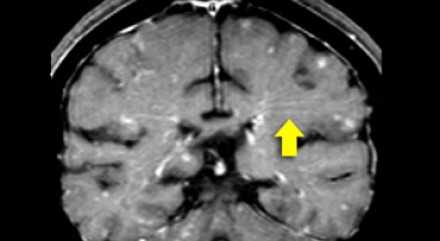

Распределение патологических участков на представленных МР-томограммах крайне напоминает рассеянный склероз . Помимо вовлечения глубокого белого вещества визуализируются юкстакортикальные очаги и даже «пальцы Доусона». В итоге было сделано заключение о саркоидозе. Саркоидоз не зря называют «великим имитатором», т. к. он превосходит даже нейросифилис по способности симулировать проявления других заболеваний.

На Т1 взвешенных томограммах с контрастным усилением препаратами гадолиния, выполненных этому же пациенту, что и в предыдущем случае, визуализируются точечные участки накопления контраста в базальных ядрах. Подобные участки наблюдаются при саркоидозе, а также могут быть обнаружены при системной красной волчанке и других васкулитах. Типичным для саркоидоза в этом случае считается лептоменингеальное контрастное усиление (желтая стрелка), которое происходит в результате гранулематозного воспаления мягкой и паутинной оболочки.

Еще одним типичным проявлением в этом же случае является линейное контрастное усиление (желтая стрелка). Оно возникает в результате воспаления вокруг пространств Вирхова-Робина, а также считается одной из форм лептоменингеального контрастного усиления. Таким образом объясняется, почему при саркоидозе патологические зоны имеют схожее распределение с рассеянным склерозом: в пространствах Вирхова-Робина проходят мелкие пенетрирующие вены, которые поражаются при РС.